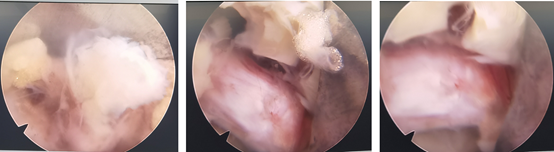

内镜下成功取出突出的椎间盘